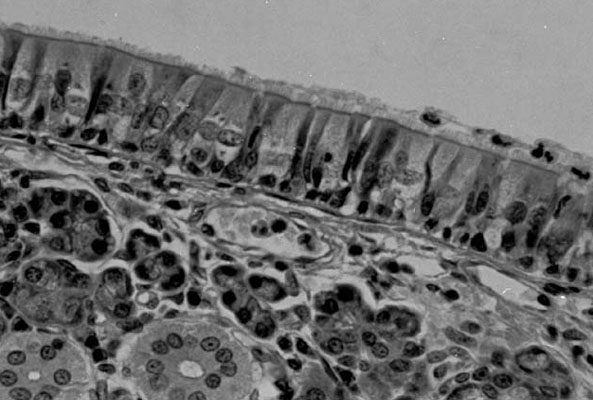

Ciliated columnar epithelium photographed with T-max 100 film through a Nikon light microscope using Köhler illumination and a single lens reflex camera. |